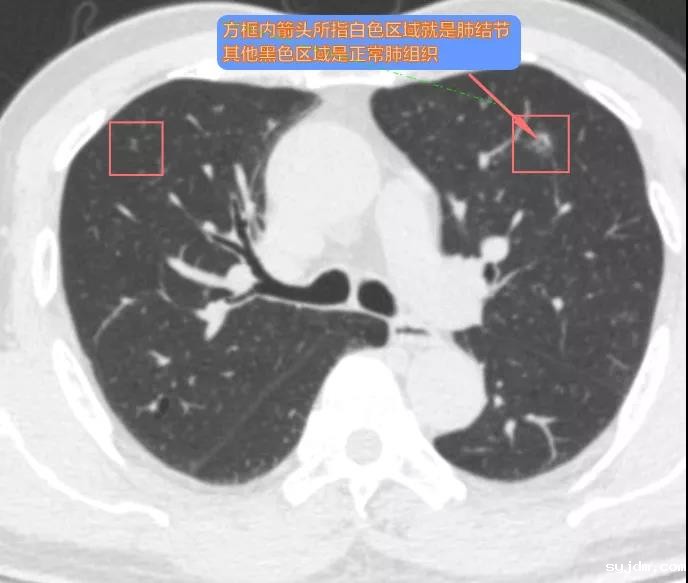

肺结节并不是疾病名称,而是一个影像学术语。结节就是局限性圆形、椭圆形或不规则形的东西,肺结节顾名思义,就是正常的肺组织内多出了一些较小的、局限的、椭圆形或不规则形的生理或病理性组织,在CT或胸片上显示类似结节的形态。

肺结节不等于肺癌,检出肺结节无需恐慌。有研究指出,我国正常人群体检肺结节检出率为20%~40%,湘雅医院熊曾教授团队在湖南省实施的早期肺癌筛查项目数据显示,人工智能(AI)辅助薄层低剂量螺旋CT(LDCT)使肺结节检出率明显提高,30~70岁体检人群肺结节检出率超过70%,但经过规范化培训的医生不会盲从AI的结果,而会给出恰当的结论,最大限度减少了过度诊断与体检人群的恐慌。事实上,最后病理确诊的肺癌患者仅为筛查总人数的1%~2%,90%的肺结节是良性的。